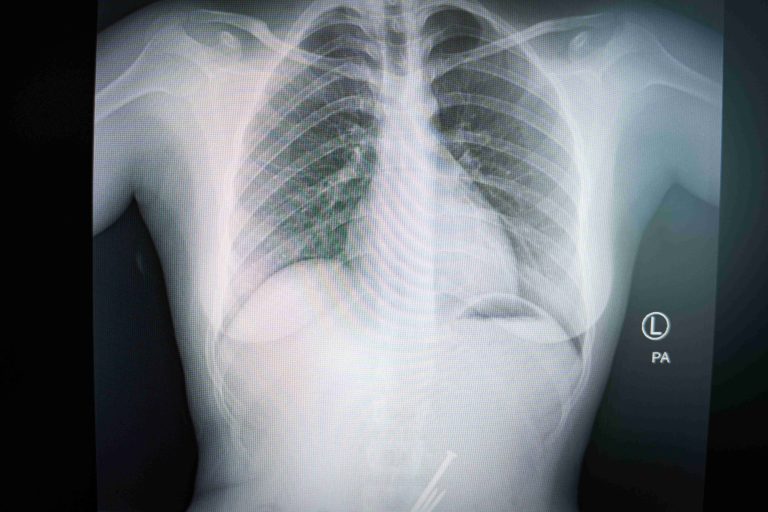

POS MB 708 3X-ray image showing a nail clipper inserted inside a uterus.POS MB 708 3$500

POS MB 708 19X-ray showing a nail clipper inside a uterus.POS MB 708 19$500